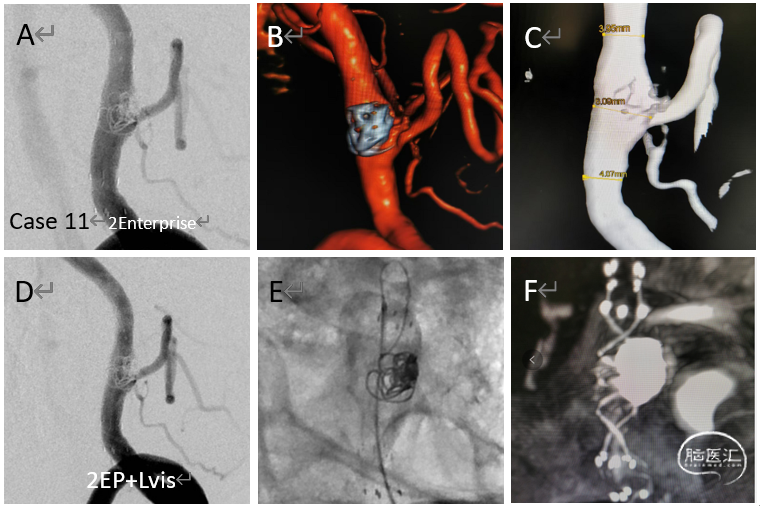

病例11

复发的累及PICA的椎动脉夹层动脉瘤

给予追加一枚LVIS,局部推密